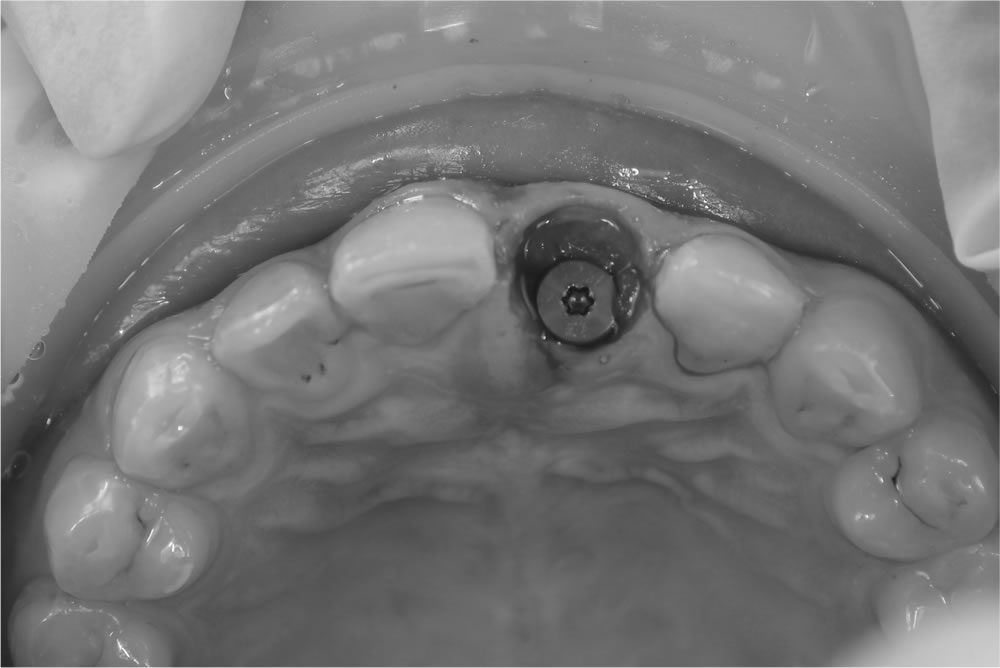

当該歯を部分的に抜歯(ソケットシールドテクニック)

ソケットシールドテクニックを用いて当該歯を部分的に抜歯しました。

手技の流れ

慎重な抜歯

歯根を割らずに、頬側部分のみを残すように抜歯。

歯根の調整

残す歯根片を滑らかに整え、周囲の骨に適合させる。

インプラント埋入

適切な位置にインプラントを配置し、残した歯根と調和させる。